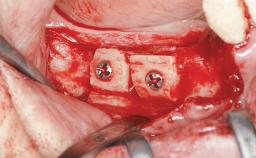

| Bone Augmentation | Horizontal|Staged |

| Augmentation Materials | Autogenous chips|Autogenous block(s)|Membrane |

| Bone Volume | Deficient horizontally, requiring prior grafting |